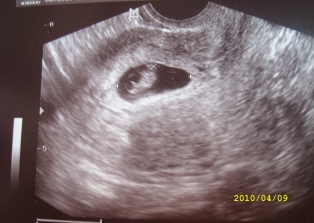

Megjöttünk az UH-ról K ügynöktől! 7 hetesek vagyunk.